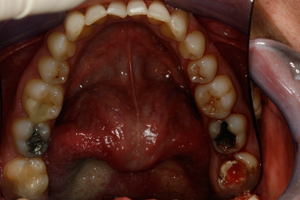

Thank you to our patients that have allowed us to show examples of our work

Have a look at just some of the many patient examples we have captured from BEFORE and AFTER their treatments and cosmetic surgeries.

From Whitening to Veneers, Fillings to Cosmetic Teeth Makeovers, here are some examples of the work that Dr. Dadabhai has provided to his patients to give them a more confident smile and a positive, pain free feeling.

Much of the work we carry out is to relieve pain and of course maintain the health of your teeth and gums, but many of our patients now ask for Cosmetic work to give them a more confident smile.

Cosmetic support has improved hugely over the last few years. Book a Consultation with Dr Dadabhai and he will prescribe a course of treatment to complete your perfect SMILE transformation.

Slide your computer mouse or finger (touch screens) over the image to view BEFORE and AFTER comparison.